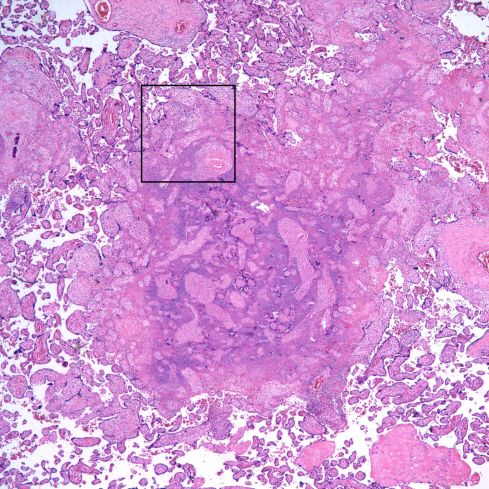

At low magnification, VUE demonstrates villi that are usually plumper than surrounding non-inflamed villi, show a loss of capillaries, and have a blue cast from the infiltrating lymphocytes and activated macrophages (Fig 6).

Fig 6) At low magnification, the area of the slide on the left shows larger, more basophilic villi typical of VUE. (H&E,4x)

A similar low magnification pattern can be seen with distal fetal vascular occlusive lesions, but the histologic features are distinct at higher magnification. In VUE, the inflammatory cells are the predominant feature and are primarily monocytic although neutrophils and even eosinophils may occasionally be present. (Fig 7,8).